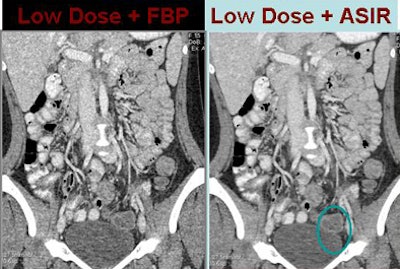

| In a15-year-old patient presenting to the emergency department to rule out appendicitis, low-dose scan with FBP reconstruction was noisier than follow-up imaging using the same dose with ASIR reconstruction. All images and data courtesy of Dr. Amy Hara. |